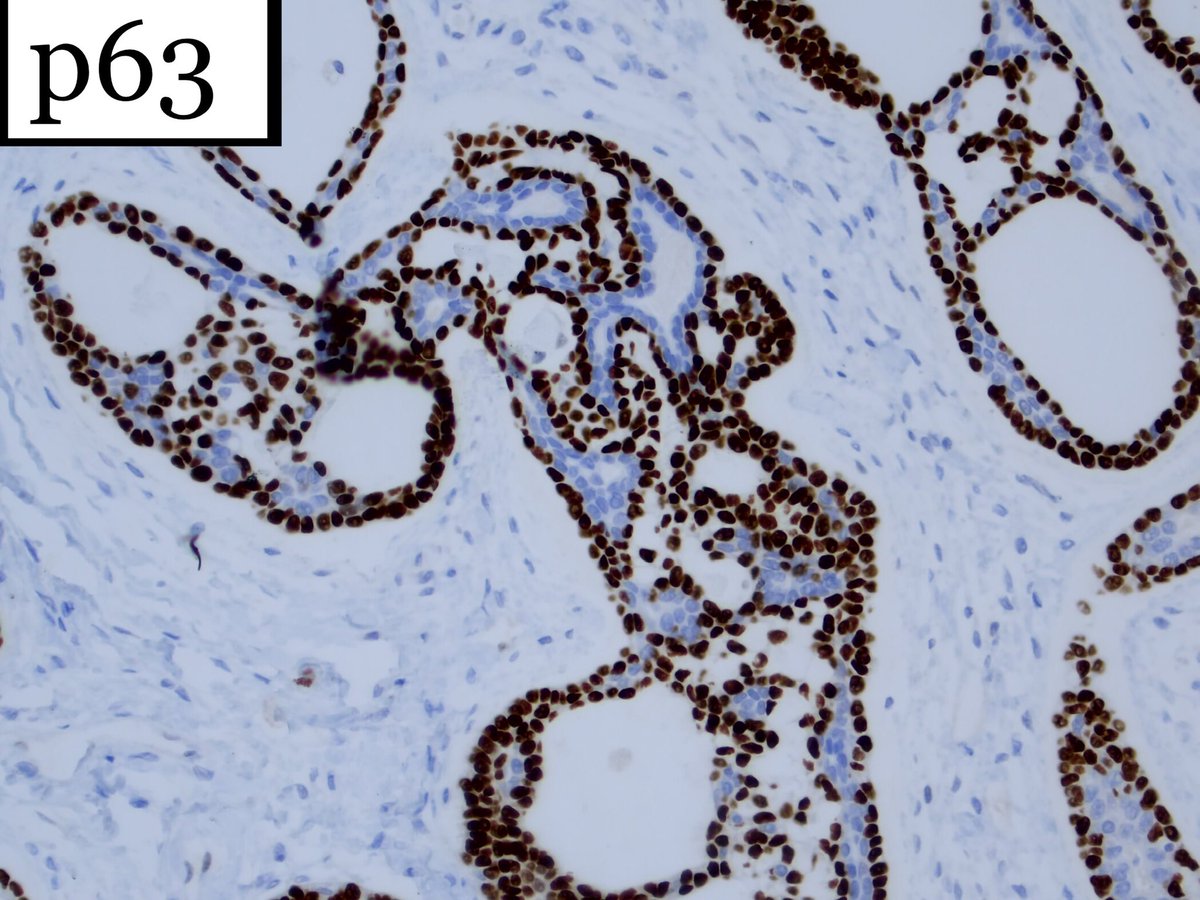

1. #Breastpath, with an #ENTpath flavor A case I had which pairs well with this sweet diagram by@TheKarenPinto (linked below) 40 year old woma